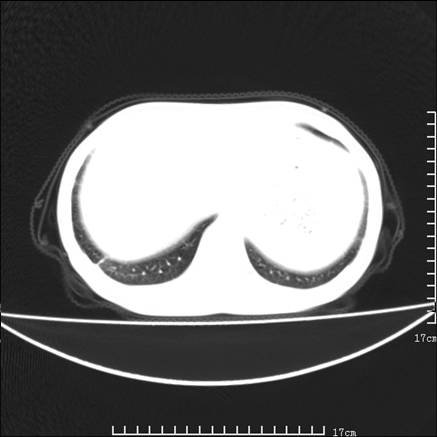

女,46岁,患胃溃疡多年,溃疡大小约1.0cm左右,后于5年前手术,病理为胃癌。主诉:半月前感冒后胸闷,气短,有咳嗽,无明显咳痰,无发热。偶有腰背部不适。

以下为高分辨扫描图像

双肺小叶间增厚,双肺散布粟米影和磨玻璃状影,以双肺上叶为重。结合病史考虑转移(癌性淋巴细管炎)可能性大。

结合病史:认为是典型肺部癌性淋巴管炎、淋巴结转移。请看图解。

肺癌性淋巴管炎征象分为主要征象及合并征象,主要征象包括:

1、近肺门支气管血管周围间质结节状增厚;

2、小叶间隔结节状增厚;

3、小叶中央间质结节状增厚;

4、胸膜下间质结节状增厚。

合并征象为:纵隔淋巴结增大,胸腔积液,肺多发随机分布的小结节等。